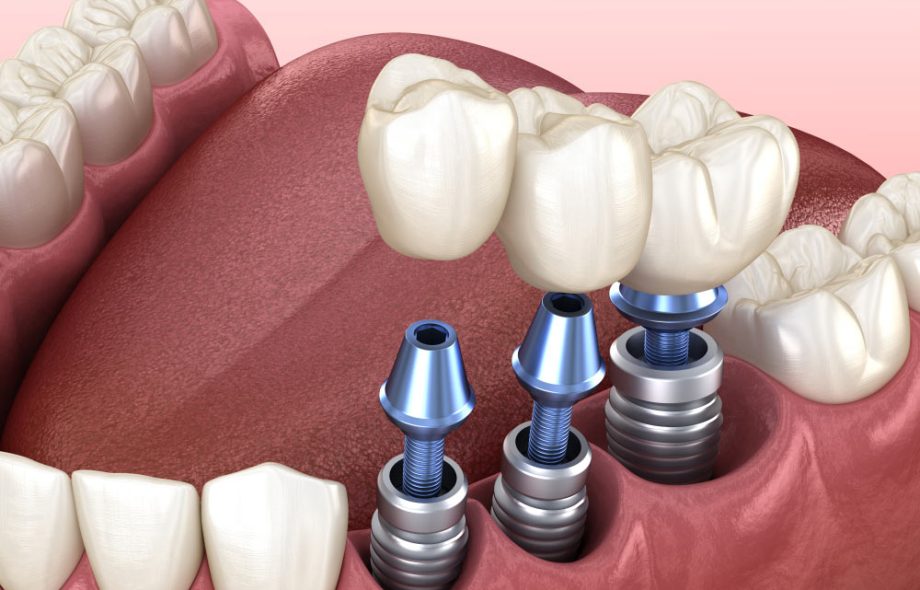

Full arch dental implants replace an entire row of teeth—either the upper or lower jaw—using a fixed bridge anchored on several implants.

Typically involves placing 4 to 6 implants per arch

Supports a permanent prosthesis that looks and functions like natural teeth

Unlike dentures, they are fixed in place and do not require removal